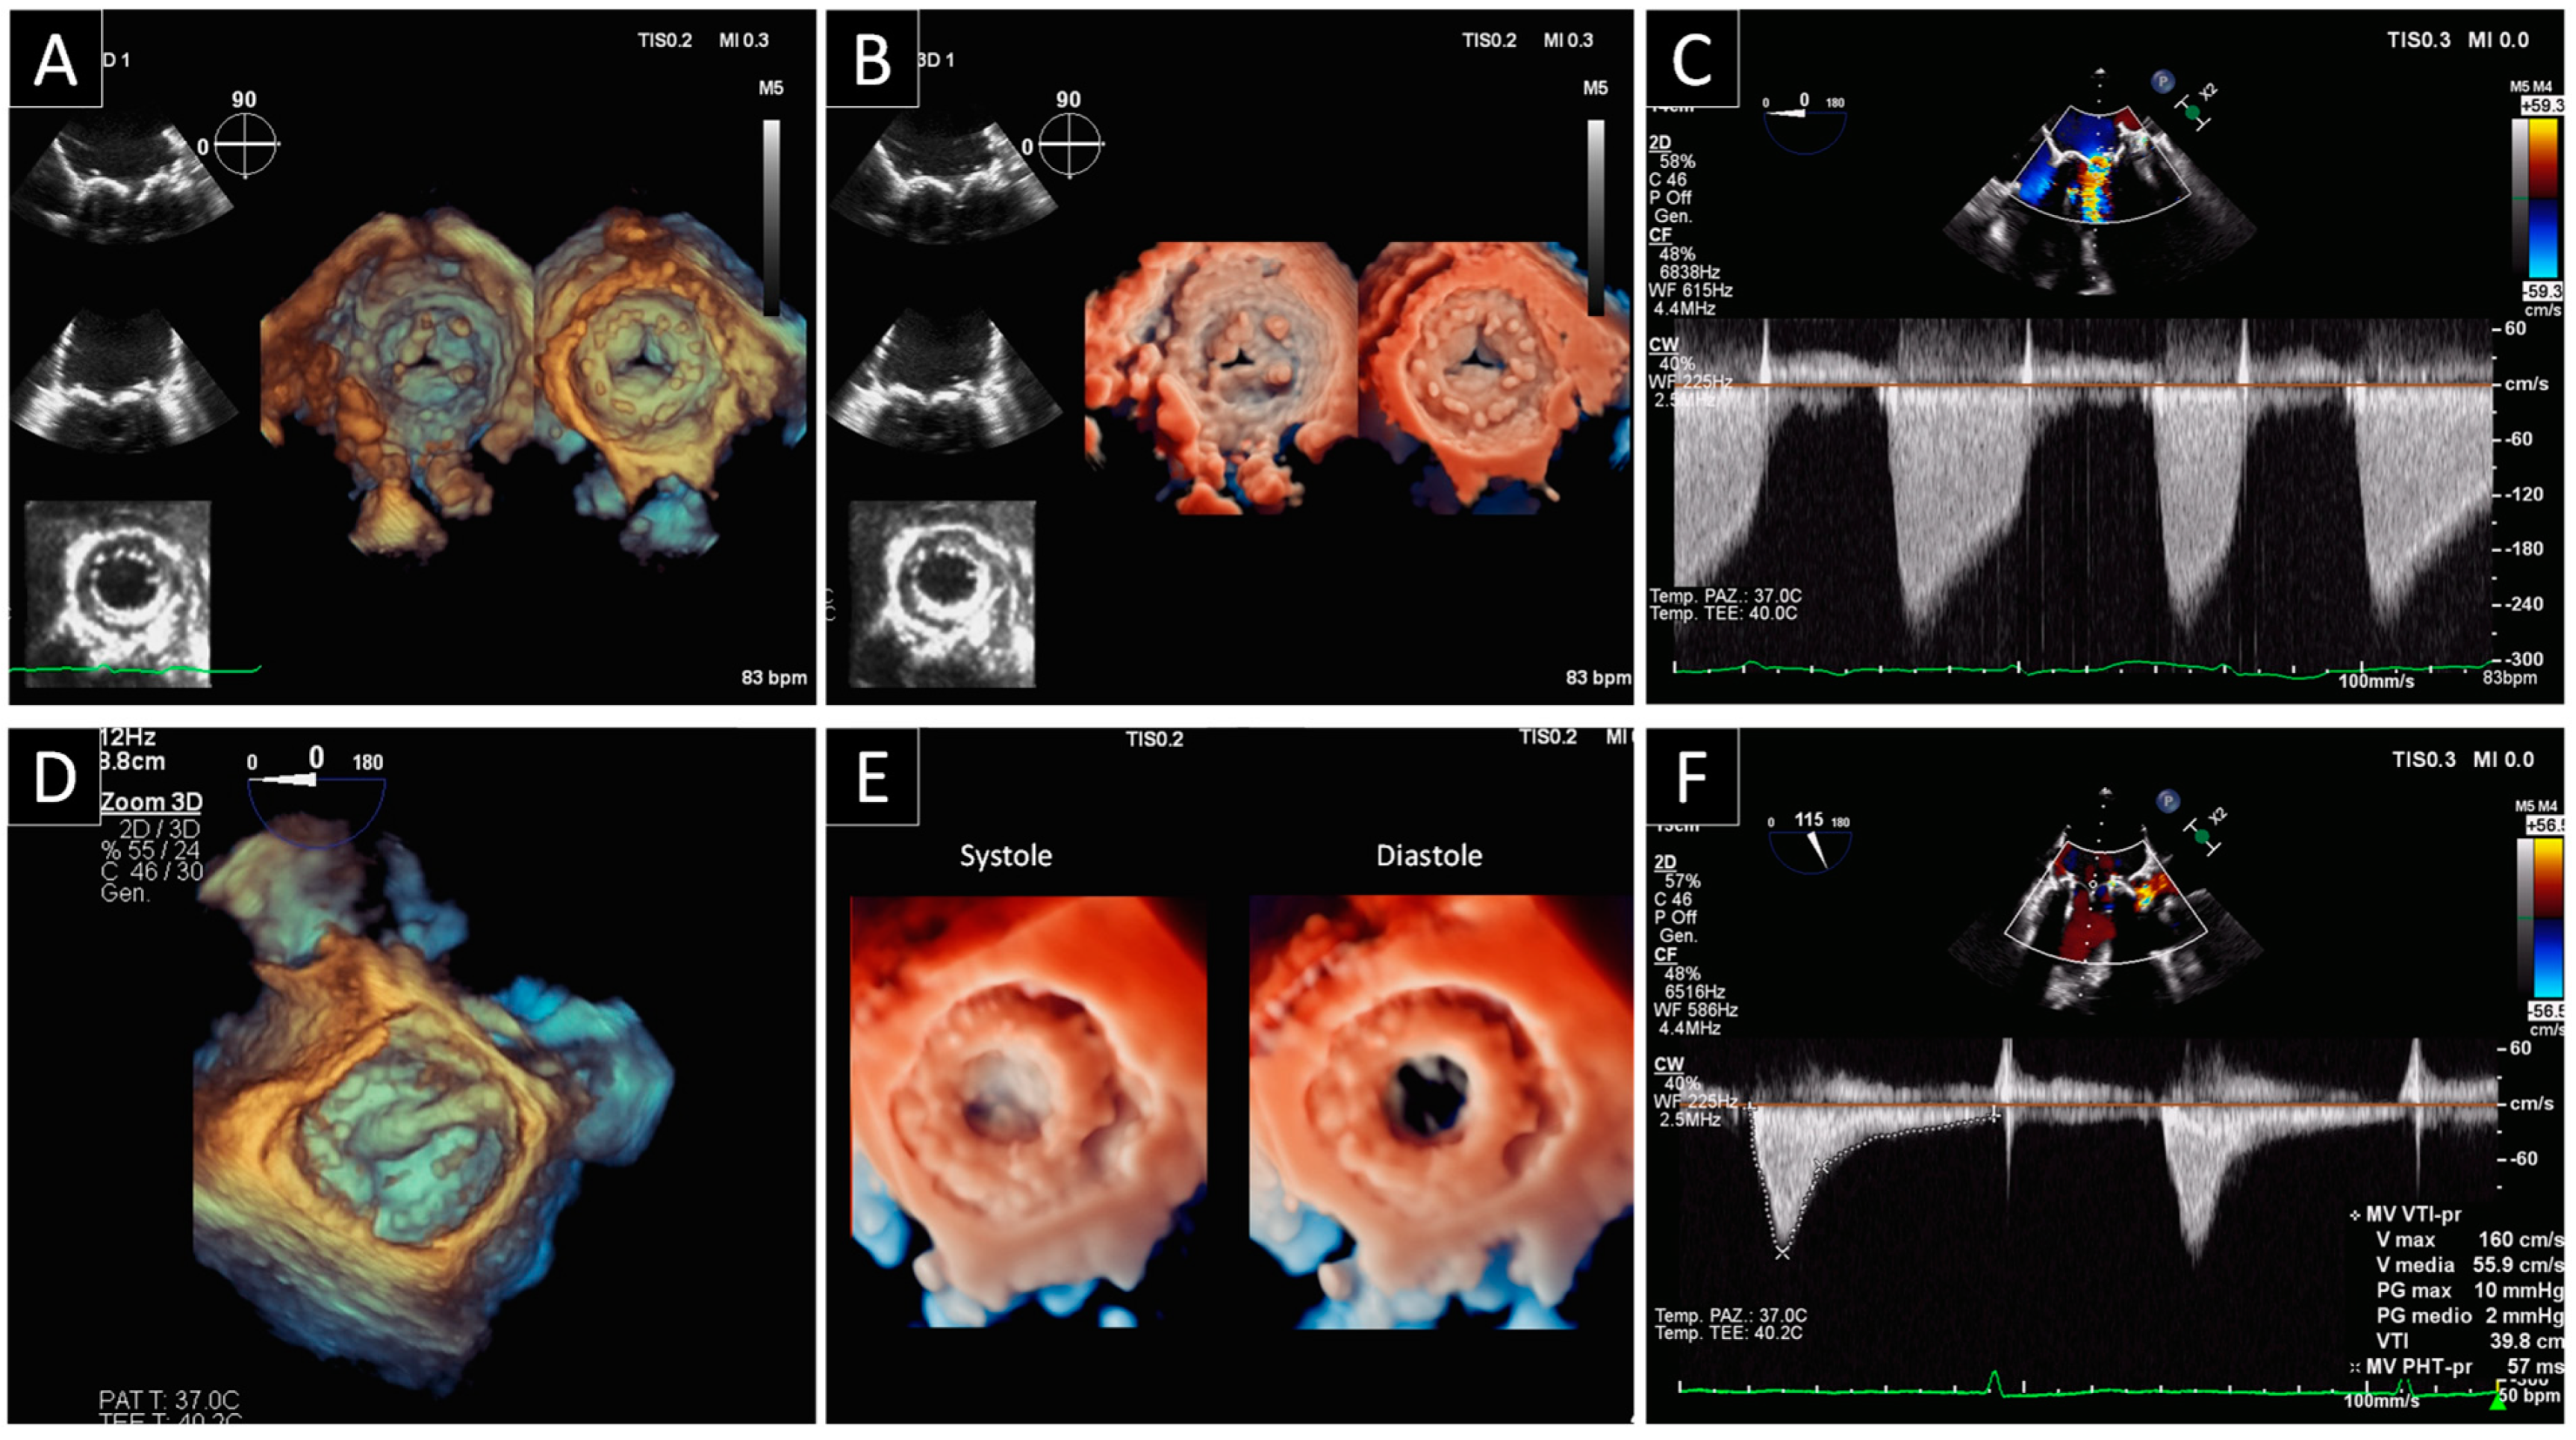

3.1. Mitral Paravalvular Leak